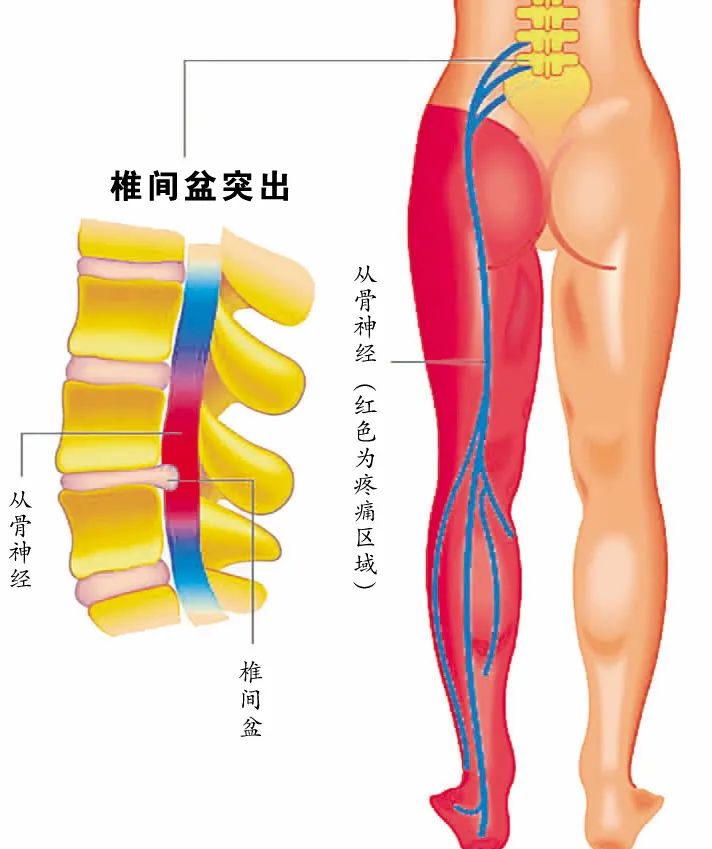

·原因: 疼痛大约在屁股摺痕处。尤其是在你膝盖伸直且将身体向前弯腰时,症状会更明显。这种型态的疼痛表示是连接到骨盆的腘绳肌肌腱受伤,这通常是因为过度的拉扯腘绳肌。(如在瑜伽中:当瑜伽练习者需要保持双腿笔直向前弯曲,然后强迫自己摆姿势时,可能最终会损伤肌腱。)当我们的肌腱受伤,腘绳肌会自然的收缩,试图去保护受伤的肌腱。然而我们认为的是:"腘绳肌紧绷又疼痛,要去伸展它,疼痛自然会消失了",而这样的方式却无法让肌腱修复,反而是重复使其受伤——过度伸展然后再受伤,这样的循环会使复原时间变更长。较好的方式是借由适当地收缩腘绳肌来增加受伤区域的循环,如果可以的话,做简单轻微的伸展。当疼痛急性期结束后,你可以慢慢增加伸展的角度。您的朋友或患者中,是否有人向你这样抱怨过:我的髋部在走路、睡觉时会痛,物理治疗师建议他作核心运动,骨科医师诊断他是梨状肌症候群,也试过请按摩师放松他紧绷的髂胫束。经过仔细的检查后,确认了他疼痛的位置,疼痛的症状都指向无力的外展肌群,造成骨盆位置不良,导致某些肌肉群去代偿。当开始训练他的外展肌群,很快地他的疼痛就不见了。此型态的疼痛通常会出现在臀部外侧或上侧,可能会向下至大腿的外侧。它通常是在散步跟晚上侧躺在患侧时更糟。薄弱的外展肌群,紧绷的髂胫束可能是引起疼痛的一种因素。这种疼痛常被认为是髂胫束的问题,所以借由伸展髂胫束,或用滚筒去放松,这会非常有效,但并没有解决问题的根源-外展肌无力,除非你去加强肌力,否则问题会一再出现。你需要锻炼你的髋外展肌,可以利用单脚站,另一侧大腿对抗重力做髋外展动作,两侧轮流施行,让髋外展肌做为稳定以及动作的功能角色。大家知道坐骨神经分布的范围到底有多大吗?它是你的身体里最长的一条神经,从下段脊椎一路延伸到脚,而且它也非常的粗,大概就像是你的小指头一样粗,穿过你的脊椎与髋关节。因为这条神经粗又长,它可能在很多地方被挤压到,而造成类似坐骨神经痛的症状。两个常见被挤压位置在下背部(腰椎椎体间)跟紧绷的梨状肌下面。梨状肌是一条很小的肌肉,当它太紧绷时可能会造成很多困扰。它位于髋部深处,在髋关节弯曲状态下,负责带动髋关节外转跟外展。紧绷的梨状肌会造成屁股痛,但当它压迫到通过梨状肌下面的坐骨神经时,就会使情况变得更糟。疼痛通常会出现在臀部中间的位置、下背部,或任何坐骨神经通过的地方。症状也有可能是脚麻或无力。如果是因为椎间盘突出引起的坐骨神经痛,是比较大的问题,超过我们本篇所要介绍的范围,在物理治疗师的指导下,加强核心肌群的运动是个不错的方式。如果疼痛是因为紧绷的梨状肌,我们可以着手于放松紧绷的肌肉。·较好的方式:利用我们常见的”收缩-放松-伸展原则”(Contract-Relax-Stretch principle)步骤①:从收缩周围肌肉开始(尤其是臀大肌),来增加此区域的血液循环。步骤②:然后我们可以轻轻的收缩梨状肌 (contract the piriformis ),让它慢慢放松掉原本慢性的收缩(如果不会感到疼痛),搭配温和的伸展。我们可以借鉴瑜伽中的动作,像是勇者式二(Virabhadrasana 2)、侧三角伸展式(Utthita Parsvakonasana)跟蚌蛤式都可以让梨状肌收缩,而在站姿下利用椅子做扭转动作,以及半鱼王式(Ardha Matsyendrasana)是伸展梨状肌最好的选择,因为此姿势会让你的脚处于弯曲、内收,但不会外转的姿势,这对于梨状肌是比较温和的姿势。步骤③:当你觉得你已经准备好在伸展加入外转的动作时,你可以选择穿针引线式(Thread-the-needle pose)来取代鸽式(Pigeon)或牛面式(Gomukasana),这会让使梨状肌受到较小的力矩。当你练习这些动作后,你就可以试着做鸽式(Pigeon)或牛面式(Gomukasana)。PS:但有些学生即使练习很久也还是没办法完成鸽式或牛面式。此外,由于过紧的内收肌群会使髋关节呈现内转姿势,使梨状肌产生额外的压力进而压迫到神经,所以也可使用相同的方式来舒缓内收肌群的慢性紧缩。紧绷的腘绳肌也会造成坐骨神经受压迫,所以对于缓解此肌群的张力也是很有效果的。请记住,即使最简易的腘绳肌伸展运动也可能造成一位有坐骨神经痛症状的人极大地疼痛,所以建议用前面提及到第一种臀部疼痛的腘绳肌伸展原则。 请记住,一个疼痛症状,有可能是许多原因造成的。如果您的疼痛在你经过一番努力后,仍然存在,应该是要去寻求专业建议的时候了。